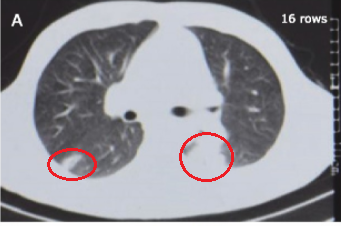

(第二次胸部CT)

一抗就是3年。

这期间患者还是有各种各样的不舒服,胃口不好,吃东西不多,觉得腹胀,乏力,胸口不舒服。时间长了,人也变得消瘦了,一看就是一个重病缠身的样子。